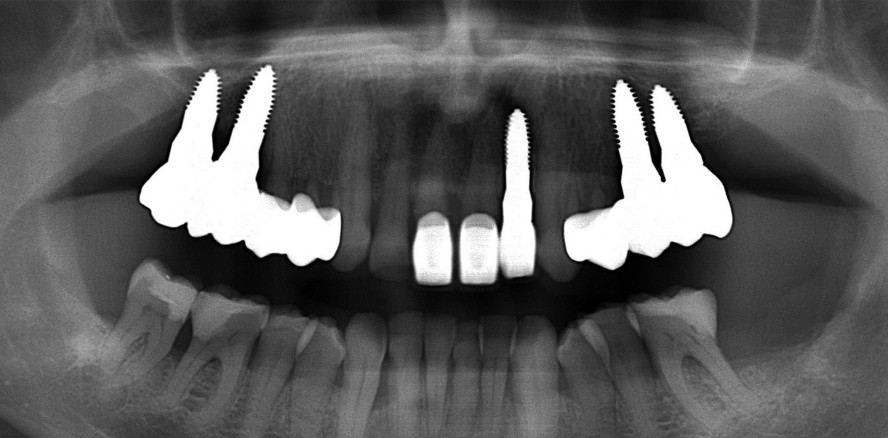

Foto: Dr. Dominik Nischwitz

Zu den lokalen Bedingungen der intelligenten Knochen- und Weichgewebsregeneration zählen die Dekontamination des Operationsgebietes (Atem, Speichel), die Aktivierung von lokalen Wachstumsfaktoren (IGF-1, Osteoblasten, Plasmaproteine etc.) durch Bohrung und Bleeding Spots (Anfrischung des Knochens) und damit Knochenstimulation sowie der Einsatz von intelligentem Biomaterial wie PRF-Membranen, um die extrazelluläre Matrix zu verbessern und die Knochen- und Weichgewebssituation zu optimieren. Der Einsatz von mikroinvasiven Techniken, wie der Piezosurgery, der Einsatz von Ozon, navigierte Implantationen, und die verbesserte Bildgebung eines DVT haben uns zahnmedizinisch-handwerklich weit nach vorn gebracht. Der Trend geht klar in Richtung Ästhetik und Gesundheit. Keramikimplantate sind kein Tabuthema mehr, sondern die Zukunft der Implantologie. Dennoch operieren bisher nur circa ­ein Prozent aller Chirurgen Keramikimplantate. Der Autor kann aus seiner zehnjährigen Erfahrung (über 4.000 eingesetzte Keramikimplantate) sagen, dass man chirurgisch, aber vor allem systemisch mehr Informationen benötigt, um eine hohe Einheilungsquote zu verzeichnen.